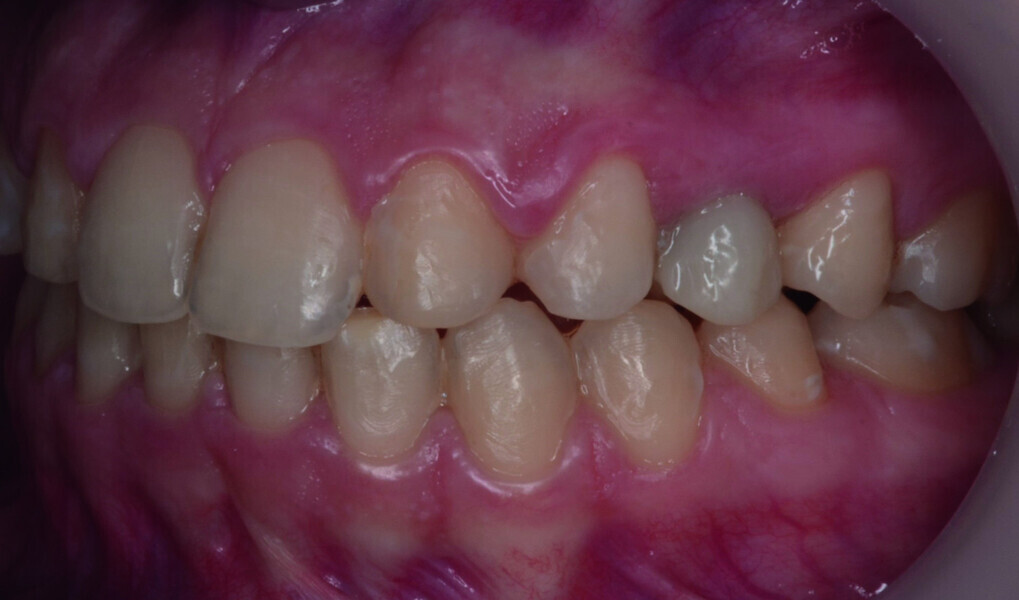

Orthodontic management of maxillary lateral incisors agenesis